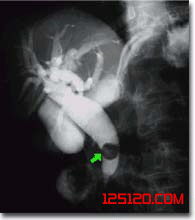

根據典型的腹痛,寒戰高熱和黃疸,結合B超檢查見膽管擴張,膽管內見結石影像的特點,肝內膽管結石的診斷多不困難。

2、B型超聲檢查見膽管擴張,膽管內見結石影像。